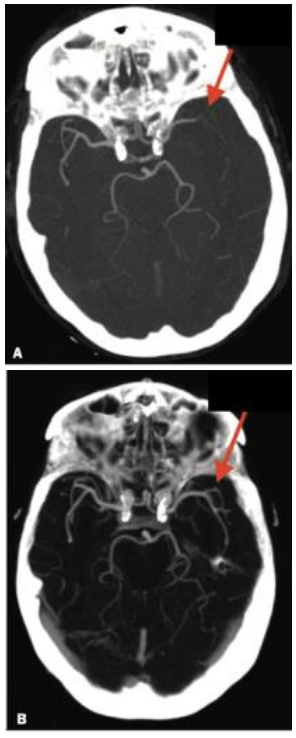

Nessa angiotomografia computadorizada de paciente com acidente vascular encefálico isquêmico agudo pode-se observar